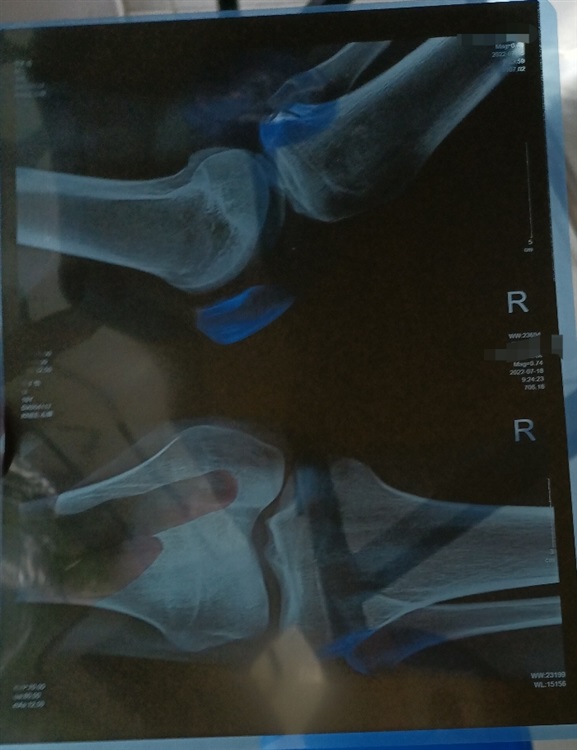

小罗今早样衰,出于莫名原因腿扭了。膝盖肿得如垫了五层的平板傲娇。

韧带跟肌肉拉伤什么什么balabala的,貌似是有撕脱性骨折的风险。